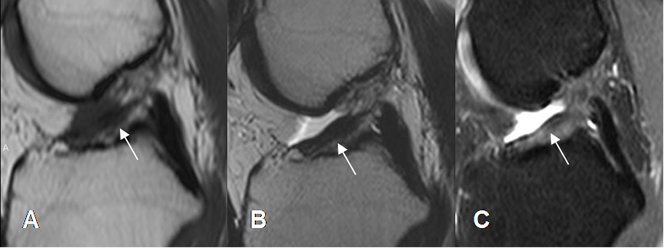

Fig 98. Ruptura crónica del LCA.

A: RM sagital en T1, B: RM sagital en T2 y C: RM sagital en STIR. Alteración en la señal y engrosamiento de las fibras, con solución de continuidad en el tercio medio, en un caso de ruptura crónica.